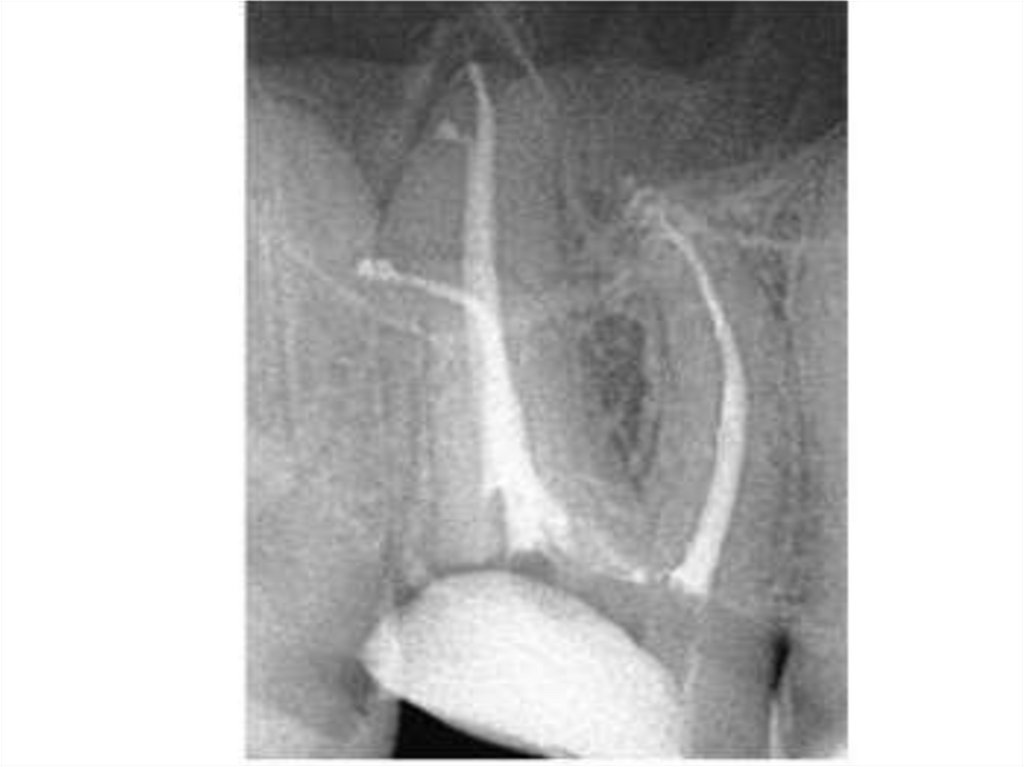

48. Пломбирование МВ2

49. 7- канальный п.в.моляр 16